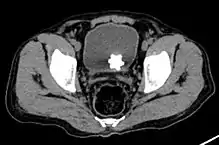

The diagnosis of bladder stone includes urinalysis, ultrasonography, x rays or cystoscopy (inserting a small thin camera into the urethra and viewing the bladder). The intravenous pyelogram can also be used to assess the presence of kidney stones. This test involves injecting a radiocontrast agent which is passed into the urinary system. X-ray images are then obtained every few minutes to determine if there is any obstruction to the contrast as it is excreted into the bladder. Today, intravenous pyelogram has been replaced at many health centers by CT scans. CT scans are more sensitive and can identify very small stones not seen by other tests.[8]